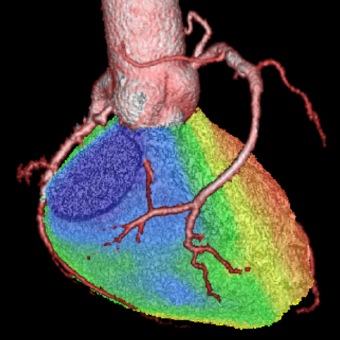

a. 心臓CT

SPECT/CT融合画像

図3 労作性狭心症症例。後側壁〜後下壁の心筋虚血はLCXおよびRCA両方の有意狭窄による。